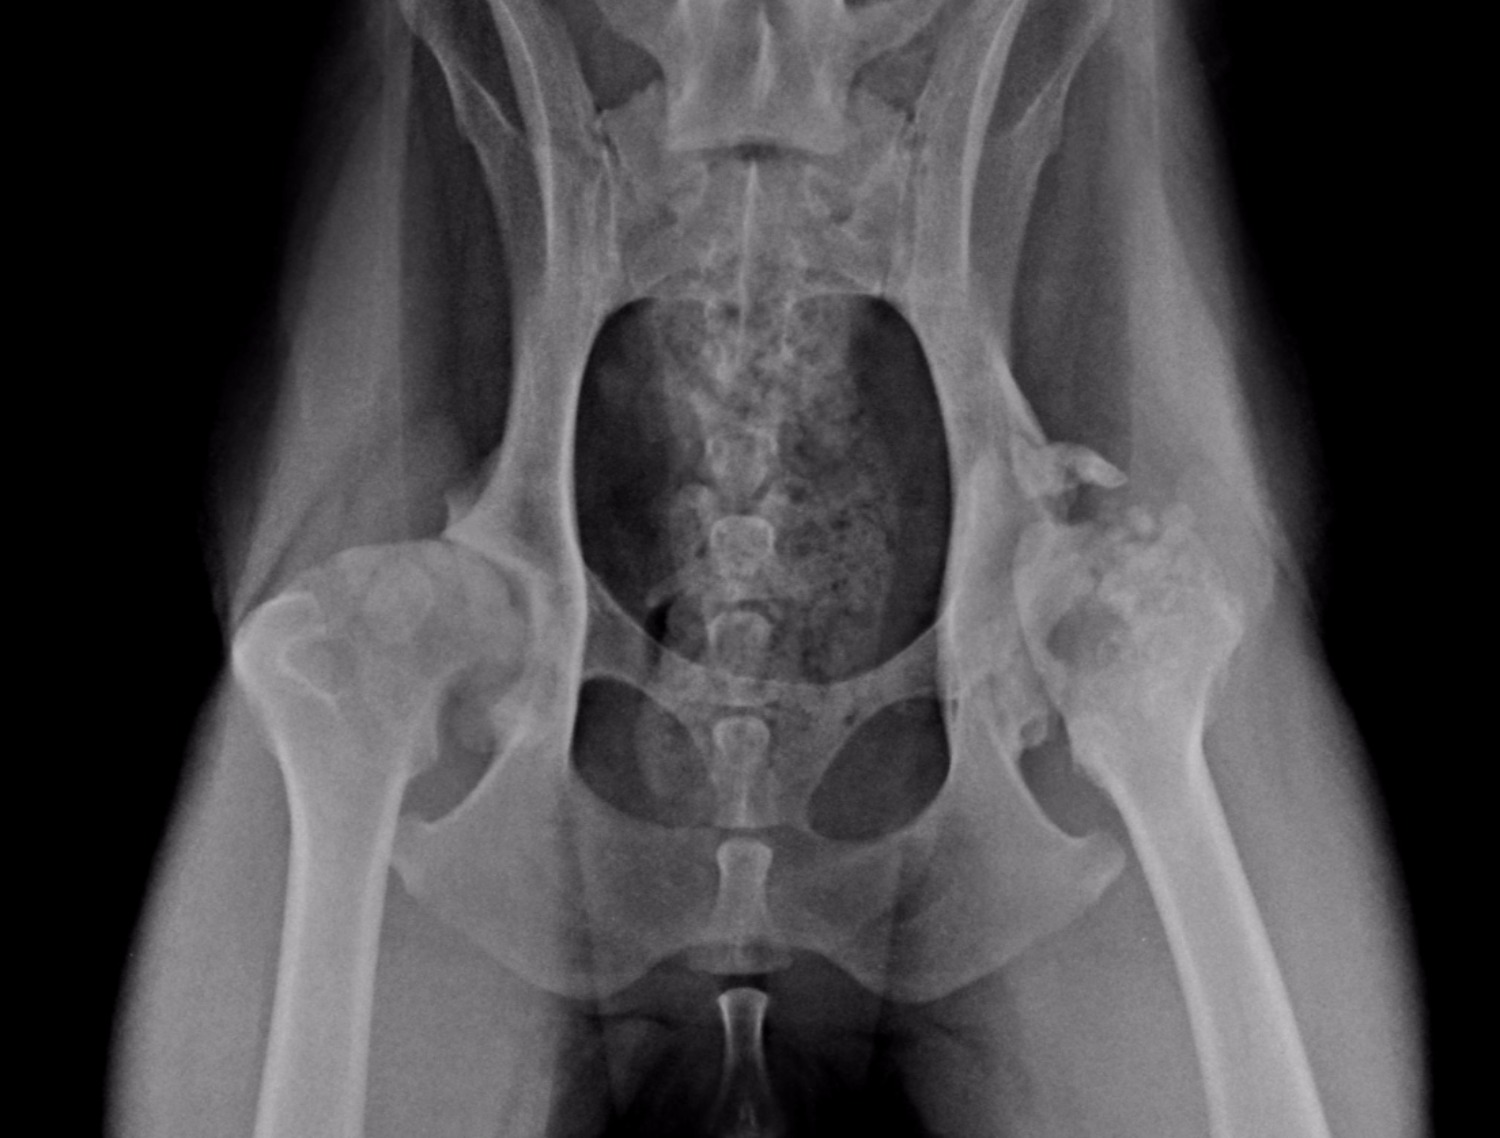

Distraction index & Canine Hip dysplasia Hip Dysplasia Dogs Cruciate Ligament anterior cruciate ligament (acl) disease (sometimes called ‘cranial’ cruciate ligament disease) is another common cause of hindleg. canine hip dysplasia (chd) is a polygenic and multifactorial. tplo cruciate ligament surgery. in one study, 32% of dogs referred to a surgeon for hip dysplasia treatment actually had a torn cranial cruciate ligament.1 let's review. learn how. Hip Dysplasia Dogs Cruciate Ligament.

OFA Grades Classification for Hip & Elbow Dysplasia Hip Dysplasia Dogs Cruciate Ligament learn how hip dysplasia affects the hip joint in dogs, especially large and giant breeds, and what you can do to prevent or treat it. in one study, 32% of dogs referred to a surgeon for hip dysplasia treatment actually had a torn cranial cruciate ligament.1 let's review. anterior cruciate ligament (acl) disease (sometimes called ‘cranial’ cruciate. Hip Dysplasia Dogs Cruciate Ligament.